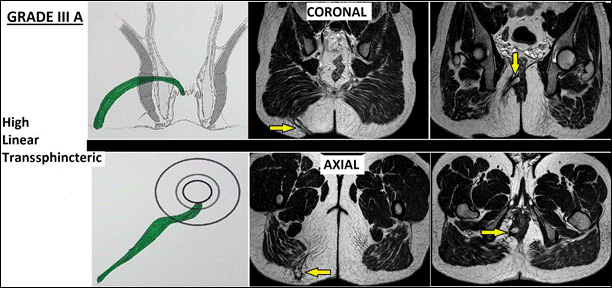

III |

Rò xuyên cơ thắt ngoài mức cao (>1/3 chiều cao cơ thắt) III-A:Rò xuyên cơ thắt ngoài mức cao dạng đường thẳng III-B:Rò kèm bệnh Crohn, tổn thương cơ thắt, sau xạ trị, hoặc rò vùng trước ở nữ |